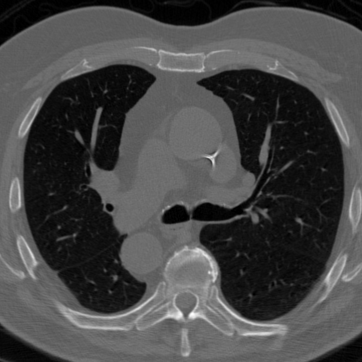

Figure 3 shows an example of a single frame of the reconstructed MR image sequences for an acceleration factor of using several approaches. We show the reconstructions that correspond to the single scalar parameter as well as to the scalar parameter pair (one spatial and one temporal) which are the parameters that maximize the PSNR of entire cine MR image and are obtained via a grid search by making use of the corresponding ground truth image. We also show the results that correspond to the parameters and which are respectively the single and the pair of scalar parameters that on average maximize the PSNR over the training set. These were obtained by treating the scalar regularization parameters as trainable parameters and training them by minimizing (33). We finally show the results for our estimated parameter-map with the proposed method. As observed, for all choices of the regularization parameters, the error with respect to the target image was significantly reduced compared to the initial zero-filled reconstruction. Further, we can see how the use of the estimated parameter-map yields the most accurate reconstruction and the best preservation of image details.

Figure 4 summarizes the results obtained over the test set with the help of box-plots. Compared to the initial zero-filled reconstruction, an improvement is clearly visible for all choices of the regularization parameter with respect to all reported measures and for all acceleration factors. In addition we see how allowing the temporal direction to be differently regularized than the two spatial dimensions positively influences the results compared to having one global parameter (orange vs blue). Last, we see how using the proposed method to estimate an entire spatio-temporal parameter-map further surpasses the scalar regularization parameter-maps (green vs orange and blue), especially in terms of SSIM. Table 1 lists the mean and the standard deviation of all TV-reconstructions. The results are consistent with the ones from the box-plots.